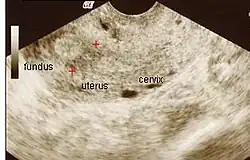

Amniotic sheet on ultrasound

The extent of adhesion formation is critical. Mild to moderate adhesions can usually be treated successfully. Extensive obliteration of the uterine cavity or fallopian tube openings (ostia) and deep endometrial or myometrial trauma may require several surgical interventions and/or hormone therapy or even be uncorrectable. If the uterine cavity is adhesion-free but the ostia remain obliterated, IVF remains an option. If the uterus has been irreparably damaged, surrogacy or adoption may be the only options.

Patients who carry a pregnancy even after treatment of IUA may have an increased risk of having abnormal placentation including placenta accreta[43] where the placenta invades the uterus more deeply, leading to complications in placental separation after delivery. Premature delivery,[37] second-trimester pregnancy loss,[44] and uterine rupture[45] are other reported complications. They may also develop incompetent cervix where the cervix can no longer support the growing weight of the fetus, the pressure causes the placenta to rupture, and the mother goes into premature labour. Cerclage is a surgical stitch that helps support the cervix if needed.[44]